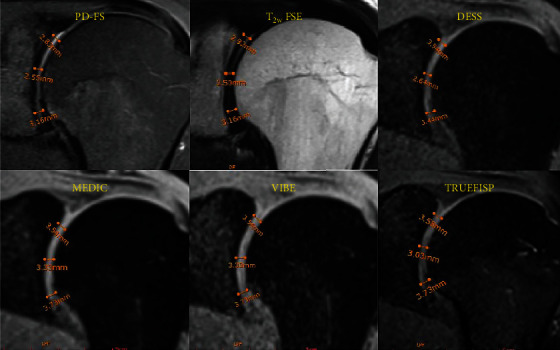

Background: Three-dimensional gradient-echo (3D-GRE) sequences provide isotropic or nearly isotropic 3D images, leading to better visualization of smaller structures, compared to two-dimensional (2D) sequences. The aim of this study was to prospectively compare 2D and 3D-GRE sequences in terms of key imaging metrics, including signal-to-noise ratio (SNR), contrast-to-noise ratio (CNR), glenohumeral joint space, image quality, artifacts, and acquisition time in shoulder joint images, using 1.5-T MRI scanner. Methods: Thirty-five normal volunteers with no history of shoulder disorders prospectively underwent a shoulder MRI examination with conventional 2D sequences, including T 1- and T 2-weighted fast spin echo (T1/T2w FSE) as well as proton density-weighted FSE with fat saturation (PD-FS) followed by 3D-GRE sequences including VIBE, TRUEFISP, DESS, and MEDIC techniques. Two independent reviewers assessed all images of the shoulder joints. Pearson correlation coefficient and intra-RR were used for reliability test. Results: Among 3D-GRE sequences, TRUEFISP showed significantly the best CNR between cartilage-bone (31.37 ± 2.57, p < 0.05) and cartilage-muscle (13.51 ± 1.14, p < 0.05). TRUEFISP also showed the highest SNR for cartilage (41.65 ± 2.19, p < 0.01) and muscle (26.71 ± 0.79, p < 0.05). Furthermore, 3D-GRE sequences showed significantly higher image quality, compared to 2D sequences (p < 0.001). Moreover, the acquisition time of the 3D-GRE sequences was considerably shorter than the total acquisition time of PD-FS sequences in three orientations (p < 0.01). Conclusions: 3D-GRE sequences provide superior image quality and efficiency for evaluating articular joints, particularly in shoulder imaging. The TRUEFISP technique offers the best contrast and signal quality, making it a valuable tool in clinical practice.